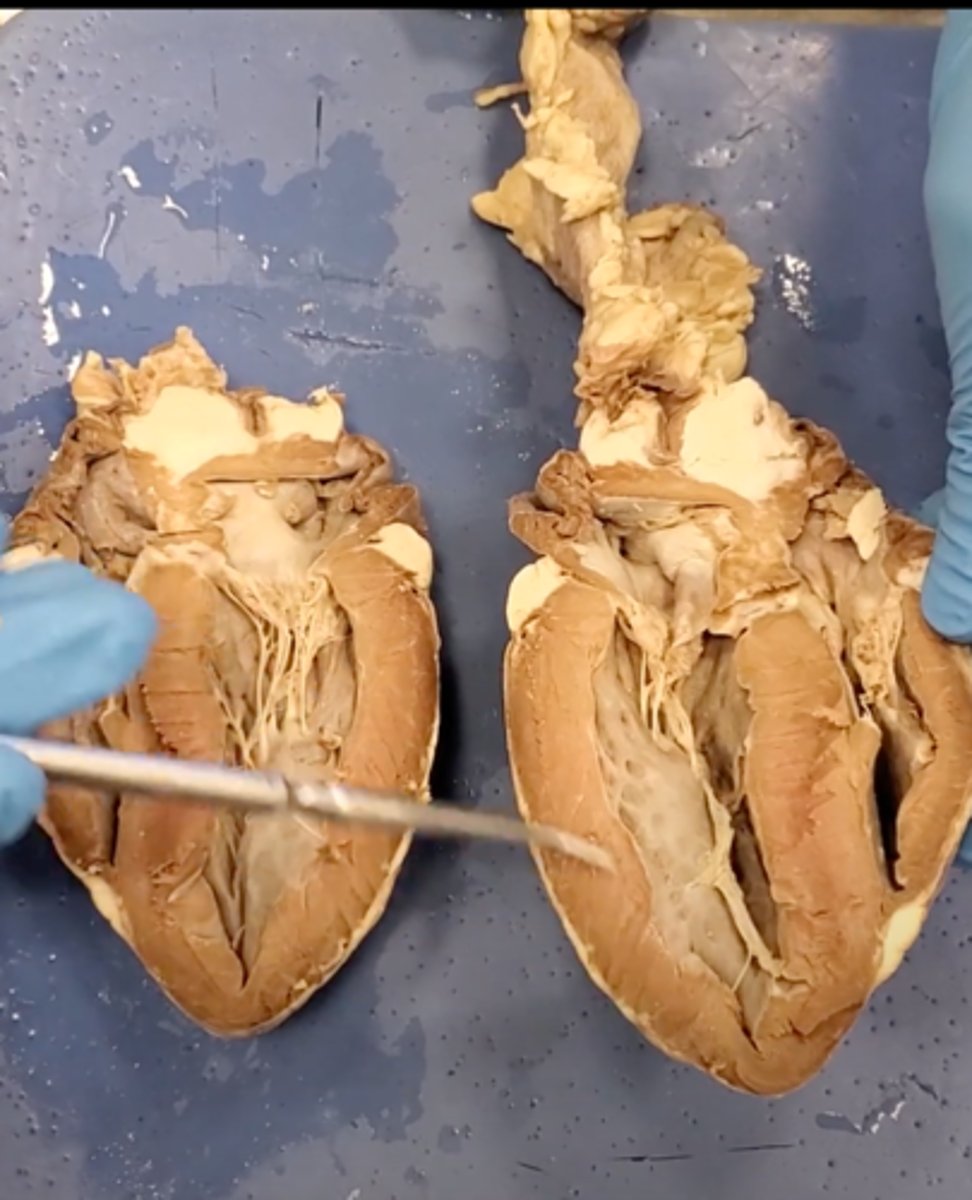

Tricuspid Valve (Right Atrioventricular Valve)

1-valve

Bicuspid valve (Left Atrioventricular Valve)

2-valve

Pulmonary Semilunar Valve

3-valve

Aortic Semilunar Valve

4-valve

Right Atrium

1-chamber

Left Atrium

2-chamber

Right Ventricle

3-chamber

Left Ventricle

4-chamber

Inferior Vena Cava

5-A vein that is the largest vein in the human body and returns blood to the right atrium of the heart from bodily parts below the diaphragm.

Superior Vena Cava

6-A vein that is the second largest vein in the human body and returns blood to the right atrium of the heart from the upper half of the body.

Aorta

7-The large arterial trunk that carries blood from the heart to be distributed by branch arteries through the body.

Pulmonary Trunk

8-carries blood from right ventricle to pulmonary arteries

Pulmonary veins

9-a vein carrying oxygenated blood from the lungs to the left atrium of the heart.

yellow sash of fat that tells you this if the front side of the heart (dissection)

pulmonary trunk (dissection)

t-shaped ribbon of fat on back side of heart (dissection)

left auricle (dissection)

right auricle (dissection)

left ventricle (dissection)

right ventricle (dissection)

right atrium (dissection)

left atrium (dissection)

bicuspid valve (dissection)

tricuspid valve (dissection)

aortic semilunar valve (dissection)

located between the left ventricle and the aorta

chordae tendineae (dissection)

thin bands of fibrous tissue that attach to the valves in the heart and prevent them from inverting